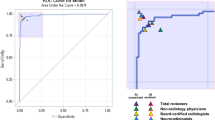

Using data from 2218 participants, we analyzed the relationship between sensitivity and FPs/case gained by changing the maximum number of candidate output points and found that the FPs/case was significantly reduced by tuning the algorithm, accompanied by a minimal decline in sensitivity (Fig. 5 and Table 5).

We found that the diagnostic sensitivity for UCA changed from 98.8 to 94.6% and the FPs/case changed from 1.986 to 1.034, thereby improving the diagnostics to a clinically acceptable level. According to a systematic review, the sensitivity of diagnosis by board-certified neuroradiologists is reported to be 87–92%22, not 100%, which is comparable to that of AI-based diagnosis. Thus, a reduction in the sensitivity of AI-based diagnosis may not be a significant problem. Accordingly, analyzing these results enabled us to visualize a significant reduction in FPs/case with a tolerable reduction in sensitivity after tuning the algorithm (Fig. 5). If the FPs/case is reduced, the burden on the diagnostic imaging physician tasked with verifying the site of the UCA diagnosed by AI will also be reduced, thereby making the AI approach more clinically feasible. Furthermore, at this level of capability, the number of diagnostic imaging physicians required may be reduced from two to one because some primary imaging physicians could then be replaced by an AI assistant for the purpose of UCA diagnosis9,12,19,20,21.

In the primary and secondary analyses, we performed Student’s t-tests for FPs/case and z-tests for sensitivity before and after tuning. FPs/case was computed as the total number of FPs divided by the total number of cases. It should be noted that this number can be higher than 1.0, since the AI can output multiple candidates per case. We plotted a histogram showing the distribution of cases for each number of FP output by the algorithm, compared before and after tuning the algorithm. The relationship between the sensitivity and the FPs/case of UCA detection following the changes in the candidate output points in each group was graphed and compared before and after tuning the AI diagnosis algorithm. The curves were obtained by limiting the number of candidates output by the algorithm to 1, 2, 3, 4, and 5 and computing both the sensitivity and average number of FPs/case in each case, resulting in 5 points for each curve.